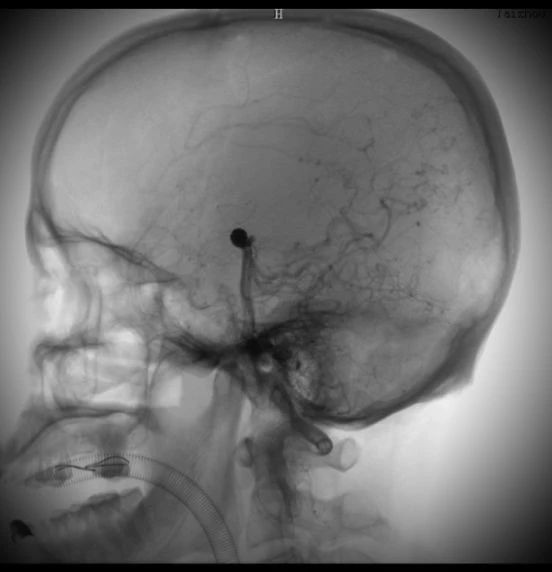

動脈瘤在這里↓↓↓

術(shù)中造影顯示的顱內(nèi)動脈瘤,大家不要小看它,它要是破裂了,可是會要人命的。所以顱內(nèi)動脈瘤又稱為腦子里的定時炸彈。

術(shù)后造影顯示,動脈瘤被致密栓塞

術(shù)后的動脈瘤長這樣。因為動脈瘤里填充了彈簧圈,所以在X線照射下整體看起來是黑色的